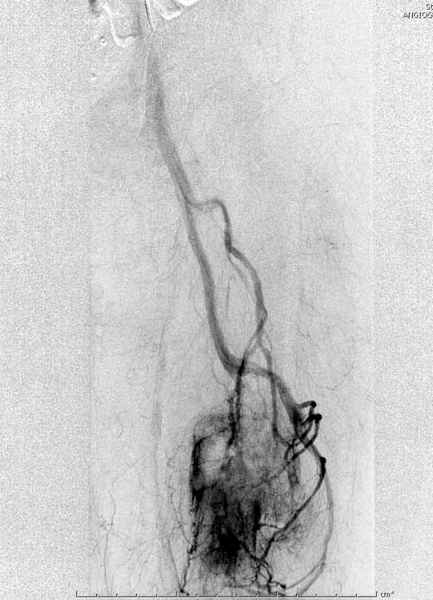

В зависимости от характера опухоли некоторые патологические переломы имеют риск кровотечения во время операции. Множественные литературные данные подтверждают, что надо проявить осторожность при интрамедуллярном остеосинтезе при неизвестных опухолях, особенно где имеется подозрение на Renal Cell Carcinoma. (RCC- hypernephroma) http://www.bonetumor.org/tumors/pages/page64.html

Со слов, больная ничем не болела, только последние 3 месяцев чувствовала боли в бедренной области. КТ брюшной полости подтвердил увеличенную правую почку. (5-6)

Для предупреждения кровотечения во время рассверливания, за день до операции провели эмболизацию сосудов питающий метастаз. http://radiology.rsnajnls.org/cgi/reprint/150/3/673.pdf (7-11, 12-15-16)

Кровопотеря во время операции меньше 100 мл.